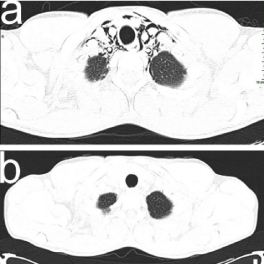

Chest X-ray (CXR) revealed clear lung fields, pneumomediastinum (PM) and emphysema in the soft tissues between the muscles of the neck (Figure 1a). Pulmonary computed tomography (CT) without contrast showed pneumomediastinum (PM), i.e. air dissecting tissue planes extending in the soft tissues of the neck, including the muscles, the nerves, the right rear second back rib and the ipsilateral front first and second anterior rib, all the mediastinal recesses (also anterior) and the bilateral peribronchial and paraesophageal spaces until the diaphragmatic hiatus. CT also showed a solution of continuity of the right postero-lateral portion of the trachea with adjacent minimum hypo-dense material (Figures 2a, 3a, 4a). In emergency department, the application of human fibrin glue by means of bronchoscopy was used to seal the tracheal lesion. CXR showed complete resolution of the PM and subcutaneous emphysema after 12 days (Figure 1b). Chest CT without contrast also revealed complete resolution at 15 days (Figures 2b, 3b, 4b).

Figure 4. Air in anterior and posterior paracardiac regions (black arrow-heads) (a) and complete resolution on chest CT scan in axial plane (b).